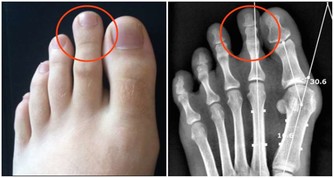

***(一)雙腿出現水腫***

當人體血管出現堵塞不通的情況,我們的雙腿下半部分就會出現靜脈曲張的問題,這是因為當人體血管硬化堵住時,毛細血管中的水分因為無法流入細胞,最終停滯在中間,才會引起下肢水腫。